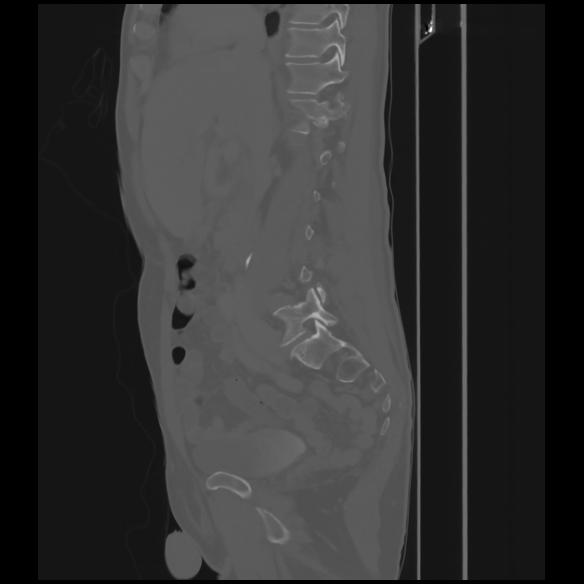

7 CUERPO,CE,Sagittal,3.000,CUERPO,Sagittal,